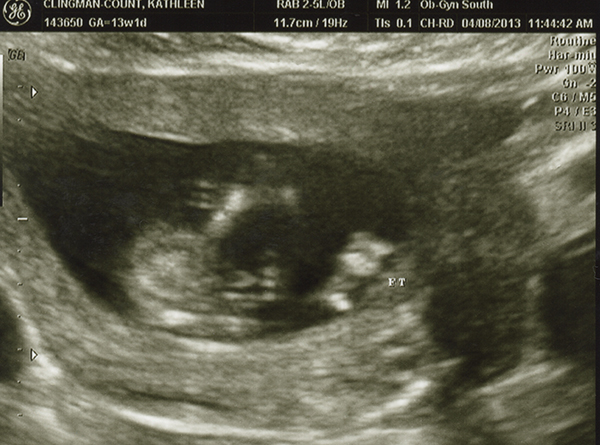

I had an ultrasound on Monday -- 13 weeks. I don't feel as though any of these are very clear pics. Even if they were better, I still wouldn't be any good with ultrasounds! Any of you experts able to make anything out with these? The tech guessed boy but the picture is not clear to me at all! She also kept saying the cord was between baby's legs and that we shouldn't go out and buy anything blue just yet. Any hope that it's a girl??

Hi Katie... Very Very hard pics not sure if there are any clues here but I will guess and say girl only because i think that potty shot looks more girl then boy but i am not an expert .

im not really sure, but I don't think the potty shot looks like a typical boy shot

Very tough to tell. I don't see a nub in the profile shot and from what ladies say on here...13 weeks just isn't great for a potty shot to be accurate. I see why the tech guessed blue, but I think it could really go either way.